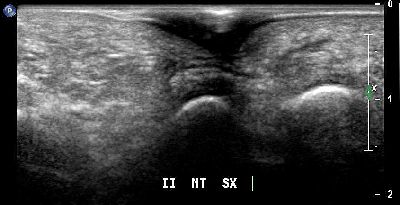

Spina calcaneare (img. 01) Spina calcaneare 01